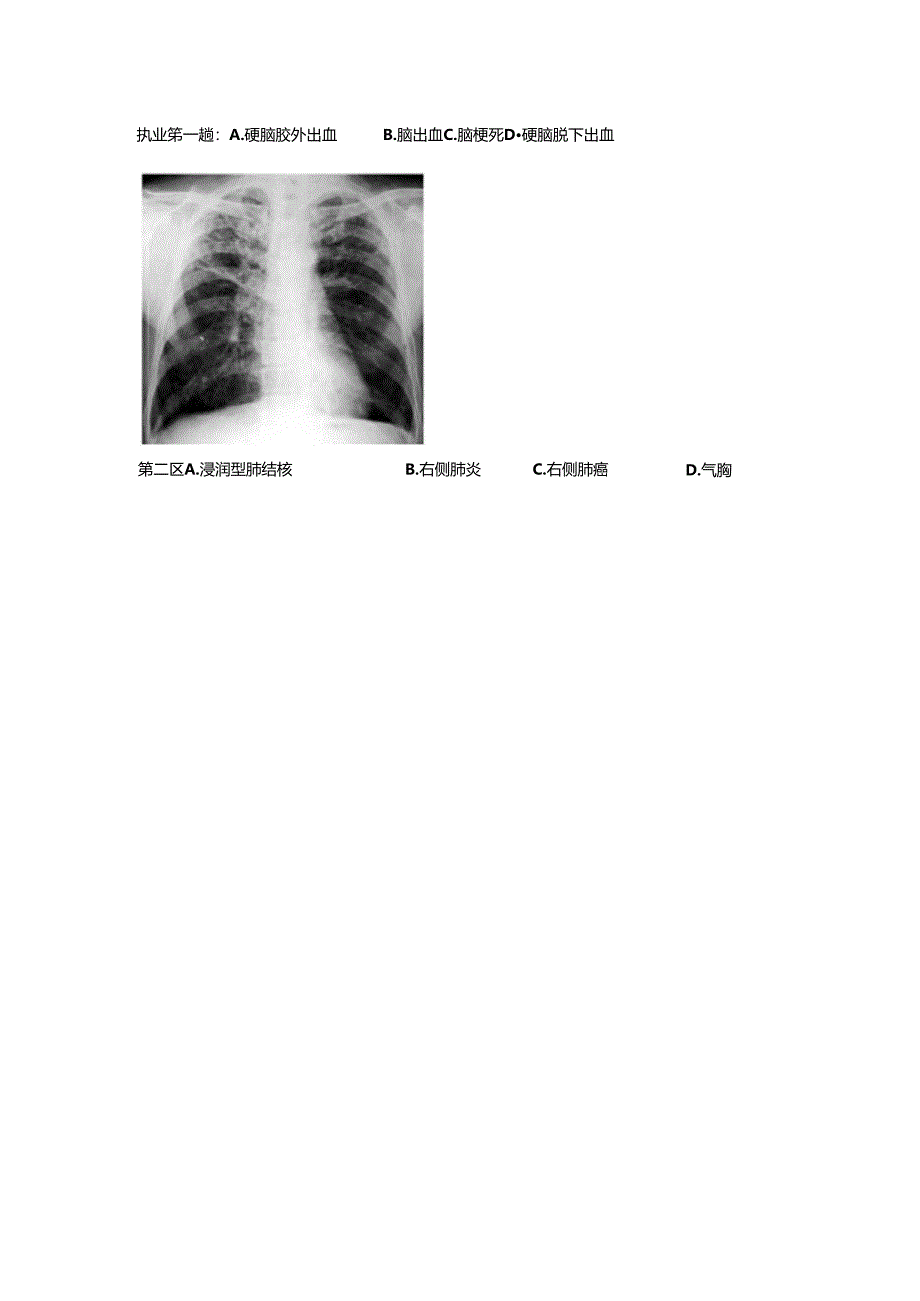

2015技能模拟临床执业第一套第三站试题卡第三站计算机多媒体考试心肺听诊(兄录青文件111-2)I.肺部听诊C胸膜摩擦音B.舒张中期春马律D.舒张早期奔马律D.干罗音A.*鼻音H.水泡音2.心脏听诊A.舒张期隆隆样杂音C.舒张晚期奔马律二)Xac执业笫一趟:A.硬脑胶外出血B.脑出血C.脑梗死D硬脑脱下出血第二区A.浸润型肺结核B.右侧肺炎C.右侧肺癌D.气胸第一:国:A.开结肠鹿B.横结肠癌C,降结肠宸D.直肠痛(三)心电图第题.诉性期前收缩B.:废I型居室传峥阻滞C.Ji(II型房室传导阻滞D.三度房室传导阻滞第二期A.正常心电图C.下壁心肌梗死B.左心室肥厚D.心肌缺血(四)医德医风患者,男性,6()岁.发现自己的尿液为红色来院就诊,医生羟过问诊后安排尿液化验.但是.患者就诊前担心自己的病怙严重,副间过有关医学的籍,担心自己患有泌尿系肿痛,询问医生精情严重程度,面对患齐的询问,作为他的主治医师,您应该怎样回答该患者?A.实话实说.诚实的面对患者.让患者接受现实.B.先安慰强齐.稔定患荷情绪.然后把实情告诉患者家属,针对患齐病情通知上级医生.C.在SJ者面前保持沉蚊,把检住结果只告诉患者家属.D.向患者I瞒病情,知为一微炎症导致.